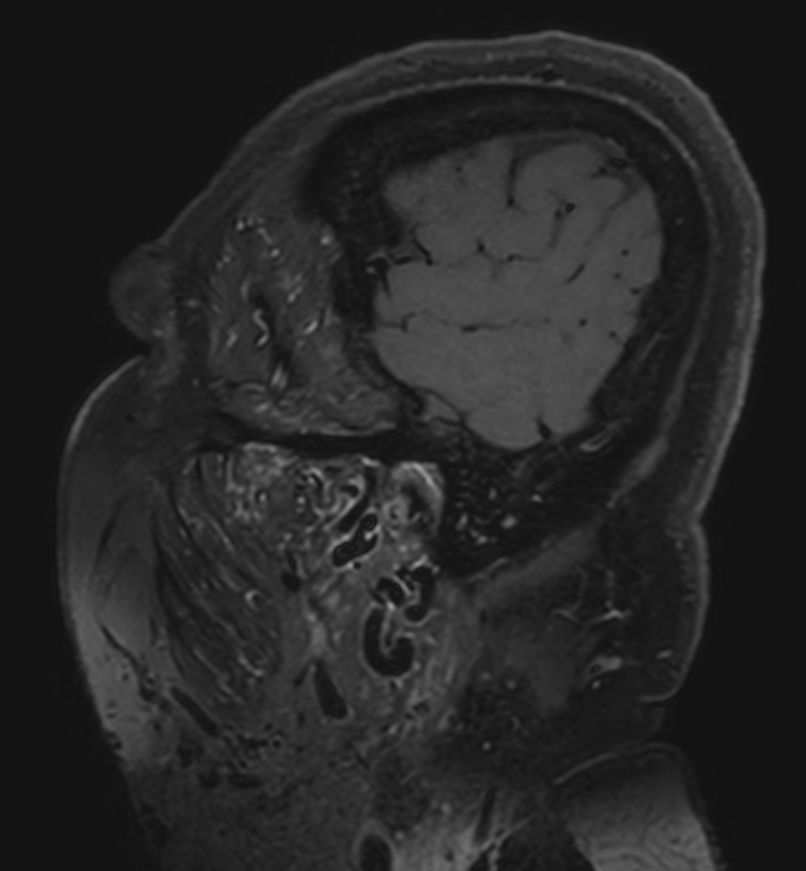

STIR MultiVane XD